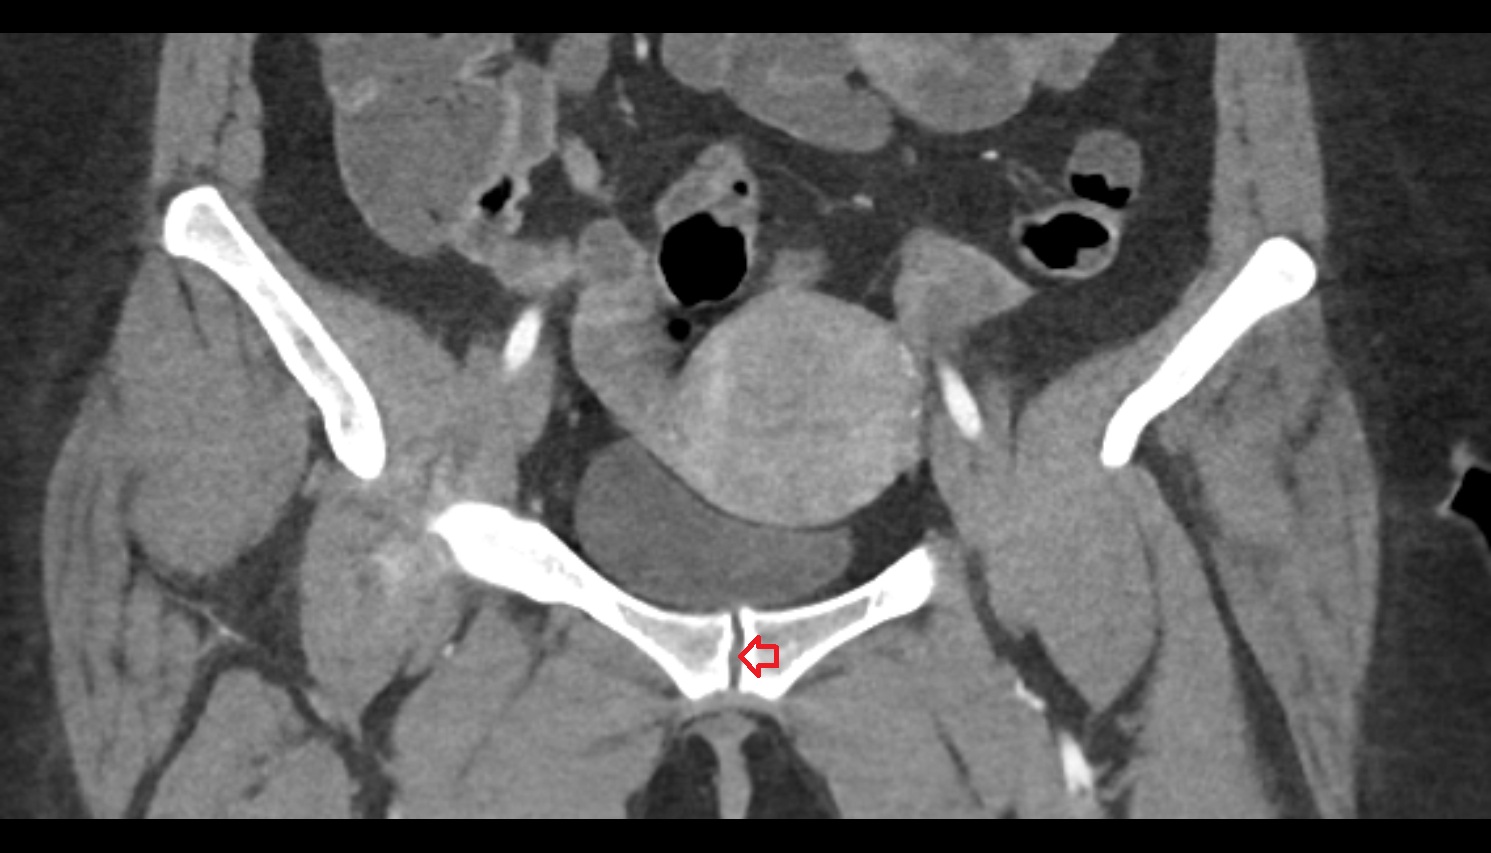

- Pubic symphysis

- Peripheral zone of prostate

- Anterior Fibromuscular Stroma of prostate

- Central zone of prostate

- Transitional zone of prostate